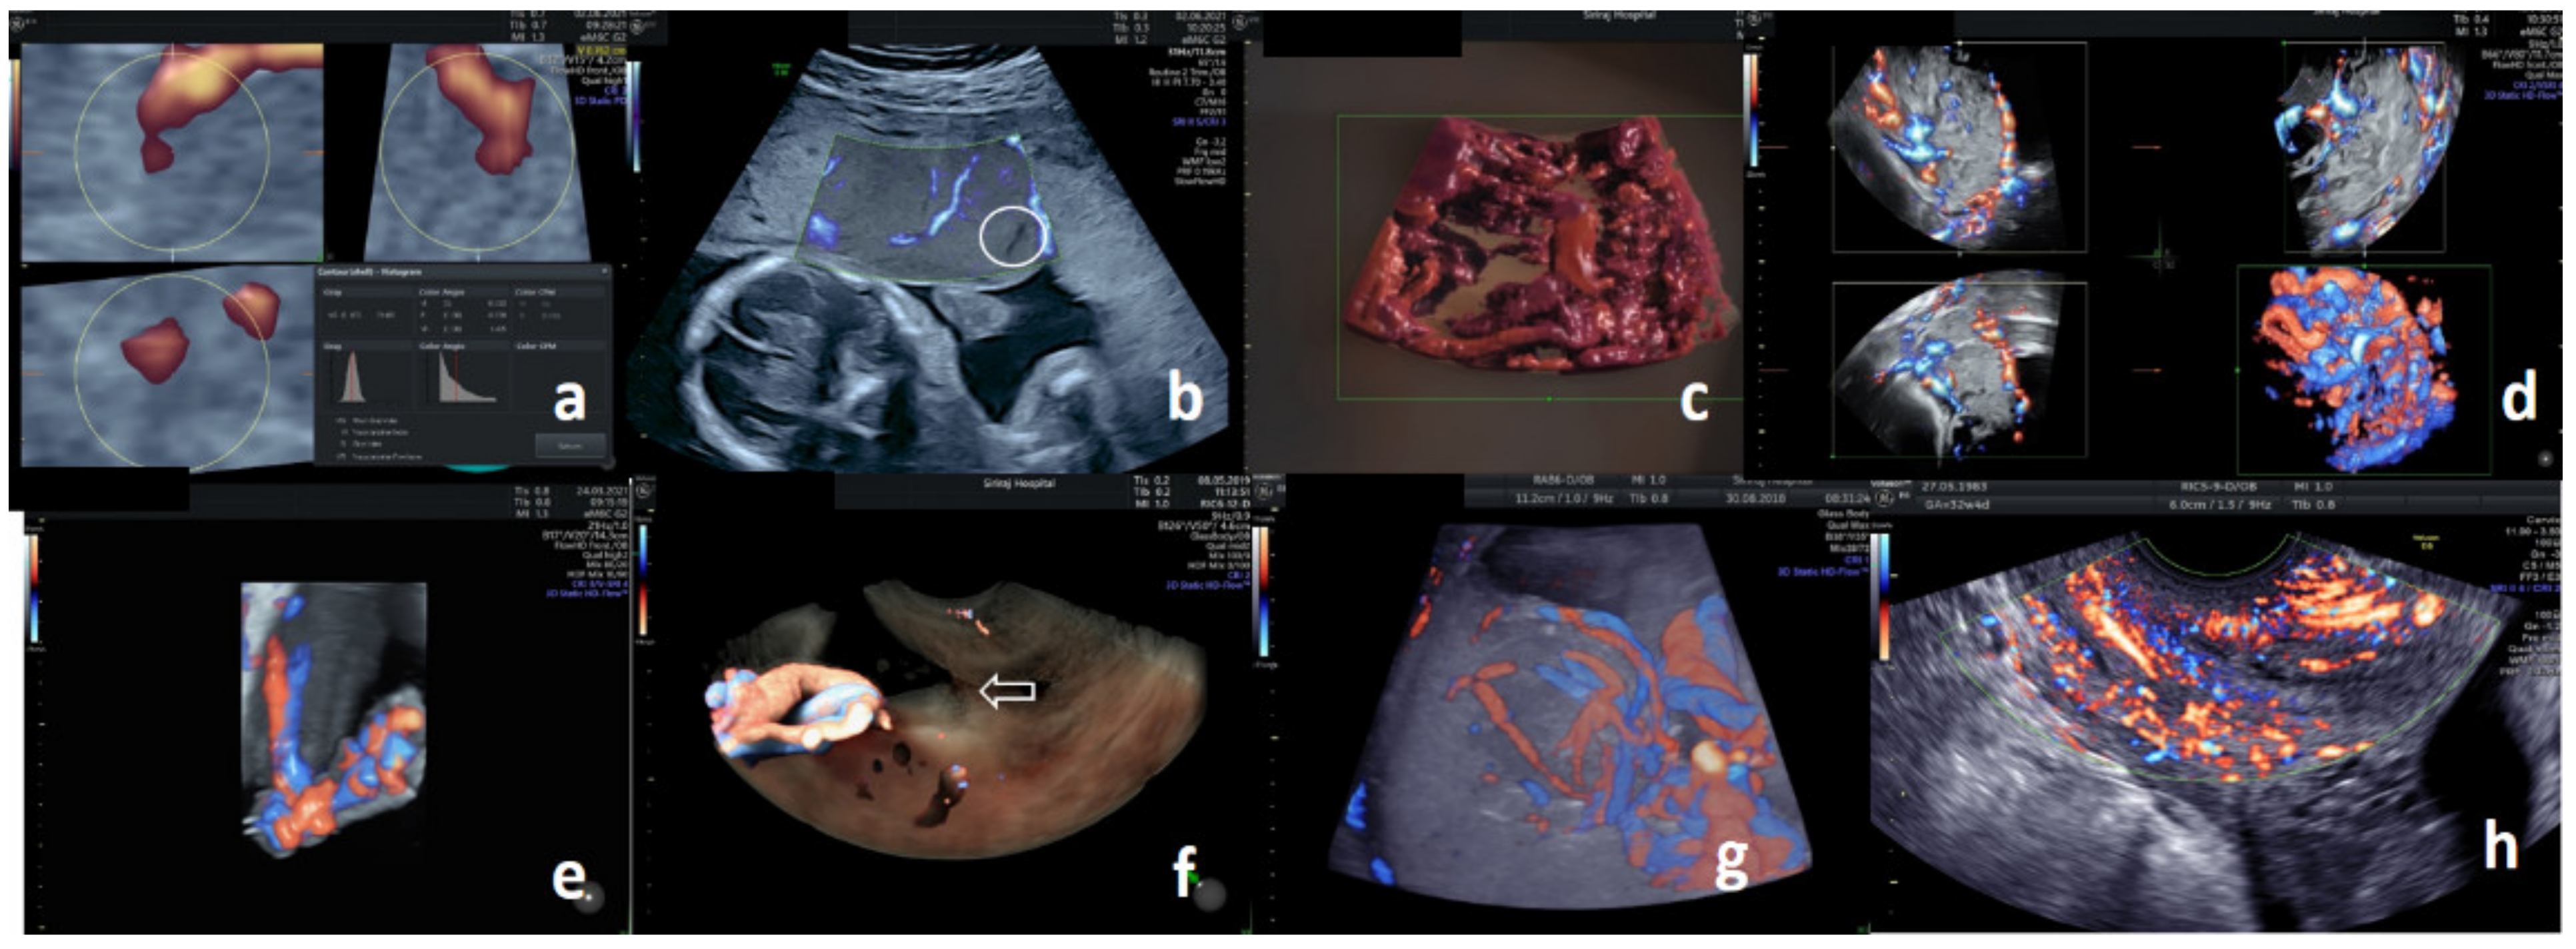

3.5. Placenta

3.6. Umbilical Cord

3.7. Cervix

3.8. Technical Perspectives